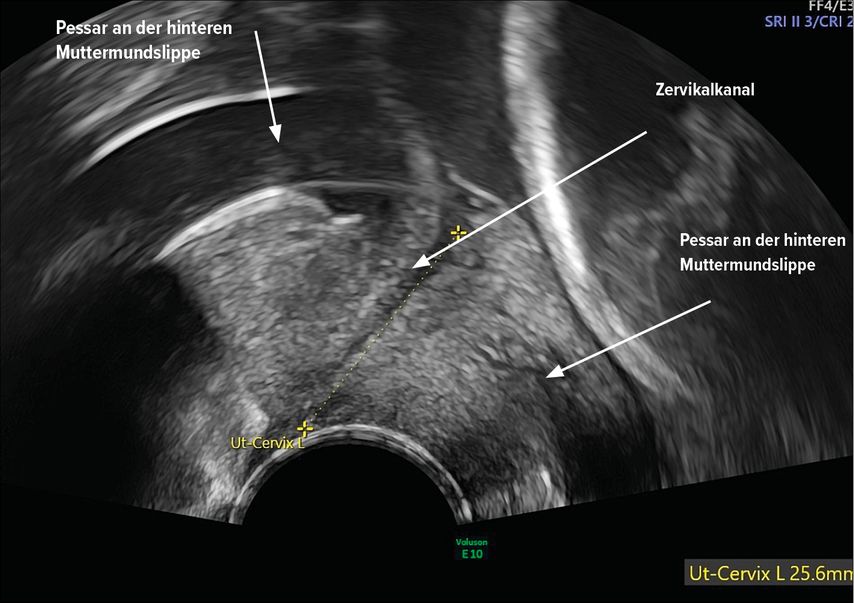

Zervixpessar

Eine Zervixinsuffizienz kann zu einem mechanischen Versagen des Gebärmutterhalses führen. Es gibt mehrere Hypothesen darüber, wie das Arabinpessar zur Vorbeugung von Frühgeburten beitragen könnte. Das Arabinpessar umschliesst den Gebärmutterhals, und verändert den Neigungswinkel des Zervikalkanals im Verhältnis zum Corpus uteri und reduziert den direkten Druck auf die Eihäute auf Höhe des inneren Muttermundes und auf den Muttermund (Abb. 2 und 3). Eine weitere Hypothese lautet, dass das Pessar den Zervixschleimpfropf schützt. Dies könnte dadurch erreicht werden, dass das Pessar die Anhaftung des verbleibenden Zervixgewebes unterstützt.19